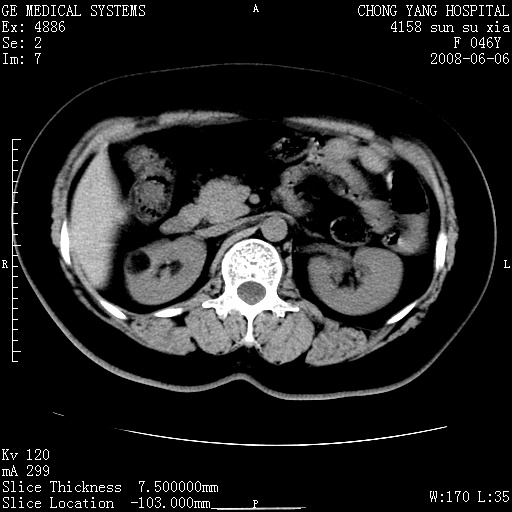

标题: CT13886:F 40Y, 外侧的CT值-60 内侧的25HU. 未作增强 [打印本页]

标题: CT13886:F 40Y, 外侧的CT值-60 内侧的25HU. 未作增强

考虑:右肾错构瘤。

右肾平滑肌脂肪瘤并肾囊肿

右肾血管平滑肌脂肪瘤并肾囊肿(后者请排除容积效应,可结合超声)

右肾血管平滑肌脂肪瘤并肾囊肿(后者请排除容积效应,可薄层扫描或结合超声)

根据影像表现,基本可确诊!